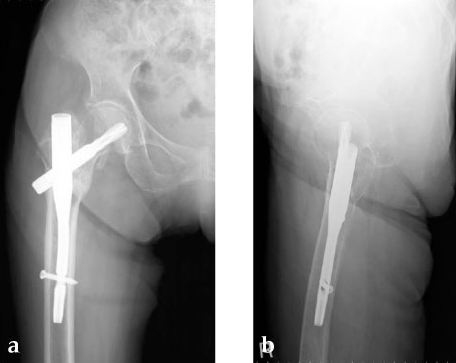

An 85-year-old Japanese woman fell down at her home. She sustained an AO 31-A2.1 fracture. The images indicate various stages of the operation, using the PFNA Asia.